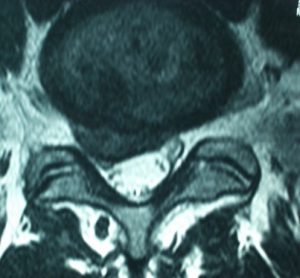

La hernia de disco o hernia discal es una afección de la columna vertebral en la que el núcleo pulposo —el material gelatinoso que se encuentra en el centro del disco intervertebral— sale de su lugar habitual debido a la rotura de la estructura fibrosa que lo contiene. Esta salida del material se produce generalmente hacia el interior del canal raquídeo, donde se encuentran la médula y las raíces nerviosas.